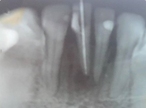

Paciente femenino de 42 años acudió a consulta tras presentar un trauma en la zona anteroinferior (pieza 4.1) con cambio de coloración, dolor persistente, aumento de volumen en la zona y no responde a las pruebas de vitalidad. En el estudio radiográfico se observó una zona radiolúcida en ápice.

Diagnóstico definitivo: Necrosis pulpar con lesión periapical.

Plan de tratamiento: Tratamiento de conductos

Descripción del tratamiento: El tratamiento de elección es un tratamiento endodontal con medicación intraconducto con Viarpex; pasta comercial de hidróxido de calcio con yodoformo. Esta medicación intraconducto se colocó y se mantuvo en el conducto durante 6 meses con citas de control cada 2 meses, junto con la ayuda de una ferulización del diente afectado con las piezas adyacentes debido a la movilidad presentada a causa de la lesión periapical. Finalmente se obturó la pieza 4.1 con la técnica de condensación lateral.

Resultados: Los resultados del análisis clínico mostraron una favorable recuperación y radiográficamente cambio en la zona apical de la pieza 4.1, sin presencia de dolor y disminución de volumen aumentado.